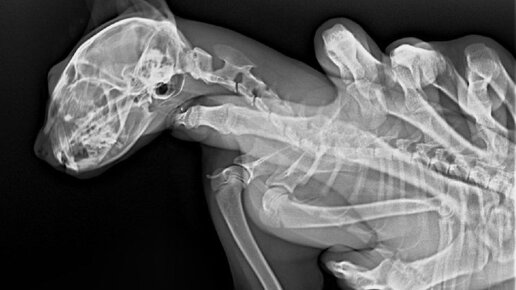

Рентген ничего не показал, но кошка продолжала хромать на одну лапку